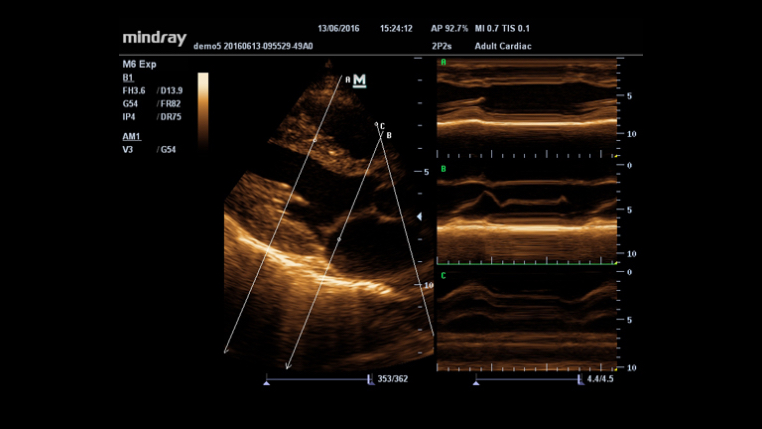

iTouch?? (Optimización de Autoimagen)

Obtenga una optimización de autoimagen instantánea en Modos B, Color y PW haciendo clic en una sola tecla.